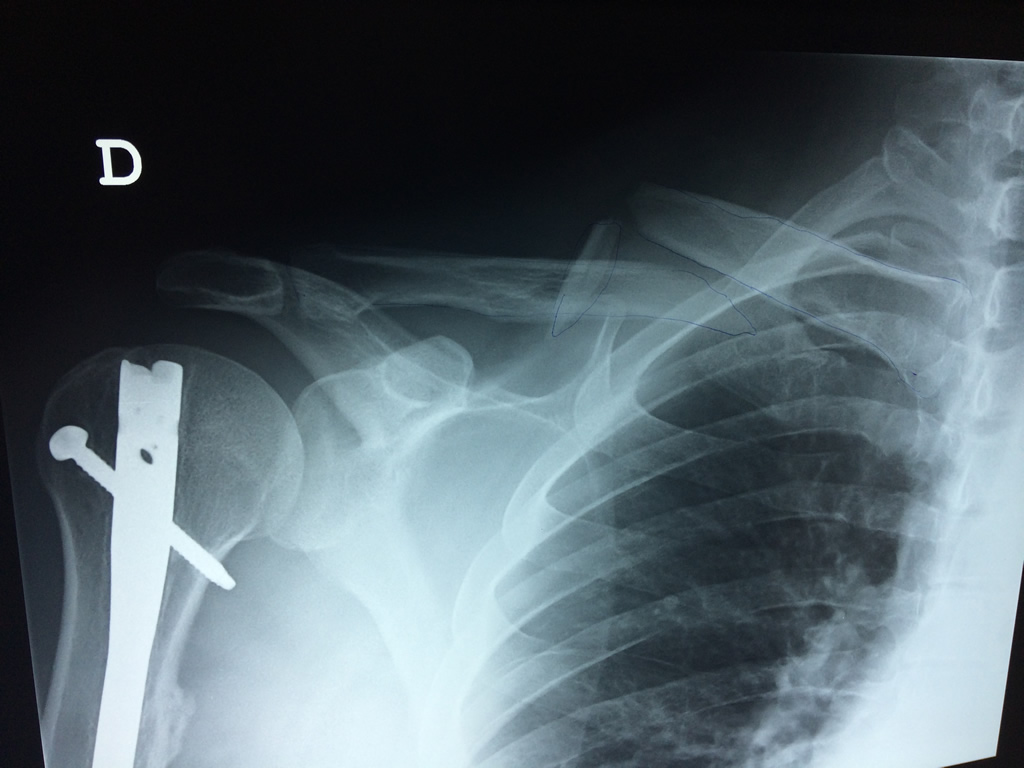

Cirugía de Fémur - Clavícula

La clavícula es un hueso largo, con forma de "S" itálica, situado en la parte anterosuperior del tórax. Junto con la escápula forman la cintura escapular. Se puede palpar por toda su longitud y se extiende del esternón al acromion de la escápula, siguiendo una dirección oblicua lateral y posterior.

Se considera el único medio de unión entre el miembro superior y el tórax. A pesar de su aspecto, similar al de un hueso largo, posee una estructura semejante a la de un hueso plano, ya que carece de epífisis y de diáfisis, lo que la harían entrar dentro de la clasificación de hueso largo. Carece de un canal medular propiamente dicho.